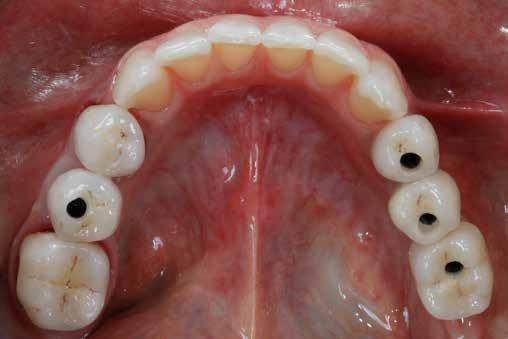

2. ábra: Az okkluzális nézet a fogszerkezet mennyiségét mutatja, a röntgenfelvételen az 1.5. fogon II. osztályú szuvasodás is látható. Még ha lehetséges is ezeket az eseteket koronahosszabbítással kezelni, a végeredmény átlagosan nem kielégítő. A ferrule gyógyulása korlátozott, és olyan parodontális szövődményekkel is találkozunk, mint a fekete háromszögek, a szomszédos fogak gyökérkitettsége. A fogszabályozó extrúzió sokkal előnyösebb.

A szakirodalomban fellelhető eredmények alapján kerámia héjak ragasztására a kontaminációtól mentes, frissen vágott zománc felszín a legalkalmasabb. A hosszú távú sikeresség elérésének további feltétele a fogak konzervatív módon történő preparálása, továbbá a ragasztás kofferdám felhelyezésével biztosított, abszolút izolálásban történő kivitelezése. Úgy véljük, hogy a fenti faktorok biztosították a cikkben bemutatásra kerülő esetek – 5 évvel az átadás után megfigyelhető – sikerességét. A kofferdám izolálás alkalmazása számos előnyt biztosít a gyakorló fogorvos számára. Megakadályozza a munkaterület nyállal, vérrel, vagy szulkusz-váladékkal történő kontaminációját, és javítja a kezelendő területre való rálátásunkat. A fogak kerámia héjak ragasztása előtt történő izolálása azonban gyakran kihívást jelenthet a kevesebb klinikai tapasztalattal rendelkező fogorvosok számára. Jelen esetbemutatásban ismertetjük a kofferdám felhelyezésének lépéseit és néhány olyan gyakorlati tanácsot, amelyek jelentősen megkönnyíthetik a munkánkat, azokban az esetekben, amikor a második kisőrlőfogak közti területet kívánjuk kofferdám segítségével izolálni. A kofferdám kapcsok segítségével került rögzítésre, majd fogakat körülvevő széleit óvatosan az ínybarázdába forgattuk. A kerámia héjak számára előkészített fogakra ragasztás előtt egyenként kapcsokat helyeztünk annak érdekében, hogy a kerámia héjak rögzítése ideális körülmények között történhessen. A lépések részletes ismertetése segítséget jelenthet – a kevesebb klinikai tapasztalattal rendelkező fogorvosok számára – az abszolút izolálás megvalósításához szükséges lágyrészmenedzsment megértéséhez. Ezek az ismeretek rendkívül hasznosak lehetnek, ha a jövőben a kerámia héjak ragasztását megfelelő módon megvalósított kofferdám izolálás mellett kívánják kivitelezni. A cikkben ismertetett módszerek alkalmazásával az abszolút izolálás megvalósítható, a gumilepedő – vérzés nélkül – ínybarázdába történő beforgatására, és a ragasztáshoz szükséges idő csökkentésére.

Az előzetes állapotfelmérést és a kezelés megtervezését követően a fogakat minimál invazív módon preparáltuk (1. a-b ábrák), majd az előkészített fogak ínybarázdáiba fonalbehelyező eszköz segítségével (113 Serrated Gingival Cord Packer, Hu-Friedy, Chicago, Illinois) teflonszalagot helyeztünk (Loctite Thread Seal Tape, Henkel Loctite Corp., Egyesült Államok), (1. c ábra). A hagyományos retrakciós fonalak helyett, a rugalmasságuk miatt előnyösebbnek tartjuk a teflonszalagok használatát. A kofferdámot (Dental Dam, Nic Tone, Bukarest, Románia) az előkészített fogakon kívül, az azoktól disztálisan elhelyezkedő egy-egy fognak megfelelően is perforáltuk.

Mivel a felső fogív első kisőrlőfogtól ellenoldali első kisőrlőfogig terjedő részét terveztük kerámia héjak segítségével ellátni (14-24), ezért az izolálást ugyanezen fogív második kisőrlőfogtól második kisőrlőfogig terjedő részére (15-25) helyeztük fel (2. a ábra). A kofferdám rögzítését a második kisőrlőfogakra helyezett kapcsok segítségével (Rubber Dam Clamps #2, Hu-Friedy, Chicago, Illinois, Egyesült Államok) biztosítottuk (2. b ábra). Ezt követően a gumilepedő fogakat körülvevő szélét kézi fonalbehelyező eszközzel és finom levegőáramlattal az ínybarázdákba forgattuk. A folyamat a következőképpen zajlott: a kézi eszközzel a kofferdámot a fognyaknak megfelelően finoman a szulkusz irányába fordítjuk, majd az eszköz végét a fognyaknak megfelelően vezetjük, miközben a lepedőt a puszterből jövő levegő segítsé-

Az általunk alkalmazott adhezív rendszerek hatékonyságát nagymértékben növelhetjük azáltal, hogy a fogakat minimál invazív módon, azaz csak zománcon belül preparáljuk, és a kerámia héjakat kofferdám izolálásban ragasztjuk. Jelen esetismertetésünknek az volt a célja, hogy bemutassuk, hogyan lehet az adekvát módon kivitelezett kofferdám izolálással megelőzni

a munkaterület nyállal, vérrel vagy szulkusz-váladékkal történő kontaminációját. A megfelelő méretben kialakított perforációs nyílások és köztük lévő optimális távolság elengedhetetlen ahhoz, hogy a kofferdámot ideális módon tudjuk felhelyezni. Ezzel az esettel azt is bizonyítjuk, hogy a gumilepedő levegőfújással, fogselyemmel és teflonszalagok segítségével történő beforgatásával az ínyvérzés kialakulását el lehet kerülni. Ismételten szeretnénk hangsúlyozni, hogy a megfelelő kofferdám kapcsok használata nélkül nem tudtuk volna a preparált csonkszélt a gumilepedő szélétől eltartani. A kezelés során elért eredményeket jól alátámasztotta, hogy a páciens az ötéves kontroll vizsgálat során teljesen elégedett volt.